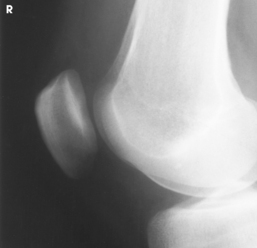

Structures shown: The resulting radiograph shows a lateral image of the distal end of the femur, patella, knee joint, proximal ends of the tibia and fibula, and adjacent soft tissue (Fig. 6-126).

Structures shown: The resulting image shows a lateral projection of the patella and patellofemoral joint space (Figs. 6-150 and 6-151).